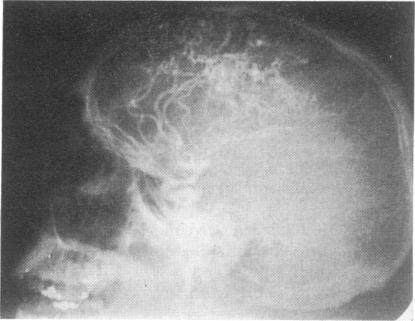

The clinical, laboratory, and other features of 16 children with congenital intracranial vascular malformations seen over a period of 15 years are presented. 13 patients had an arteriovenous (AV) malformation, 2 patients an aneurysm of the vein of Galen, and 1 a congenital internal carotid/internal jugular fistula. Based on onset of symptoms the patients ranged in age from 3 months to 16 years with an average age of 7½ years; however, 5 patients had their first clinical manifestation before 6 years of age. Unfortunately, definitive diagnosis could not be made until an average of 15½ years. The most important clinical manifestations were focal or generalized seizures and spontaneous intracranial bleeding, each occurring in 6 patients. Of 2 patients who presented with hydrocephalus, 1 had had an unexplained episode of cardiac failure during infancy. Inequality in the size of the legs, and periodic headaches were the initial manifestations in 2 other patients. Analysis of this series of patients with intracranial AV malformations suggests the following diagnostic recommendations: careful auscultation of the skull for bruits should be performed in all infants and children with cardiac failure of unknown aetiology; patients with focal seizures refractory to anticonvulsant therapy should be re-examined at frequent intervals to detect focal neurological deficit which otherwise may go unnoticed; and, finally, patients with a seizure disorder who develop focal signs of neurological deficit deserve a complete diagnostic investigation, including contrast studies.

本文介绍了15年间收治的16例先天性颅内血管畸形患儿的临床、实验室及其他特征。13例为动静脉畸形(AVM),2例为大脑大静脉瘤,1例为先天性颈内动脉/颈内静脉瘘。根据症状出现时间,患者年龄从3个月至16岁不等,平均年龄为7.5岁;然而,5例患者在6岁前首次出现临床表现。遗憾的是,平均在15.5岁时才得以确诊。最重要的临床表现是局灶性或全身性癫痫发作和自发性颅内出血,各有6例患者出现。2例表现为脑积水的患者中,1例在婴儿期曾有一次不明原因的心力衰竭发作。另外2例患者的初始表现是双下肢不等长和周期性头痛。对这组颅内AVM患者的分析提出了以下诊断建议:对于所有病因不明的心力衰竭婴幼儿和儿童,应仔细听诊颅骨有无杂音;对抗惊厥治疗无效的局灶性癫痫患者应定期复查,以发现可能被忽视的局灶性神经功能缺损;最后,患有癫痫且出现局灶性神经功能缺损体征的患者应进行全面的诊断检查,包括造影检查。